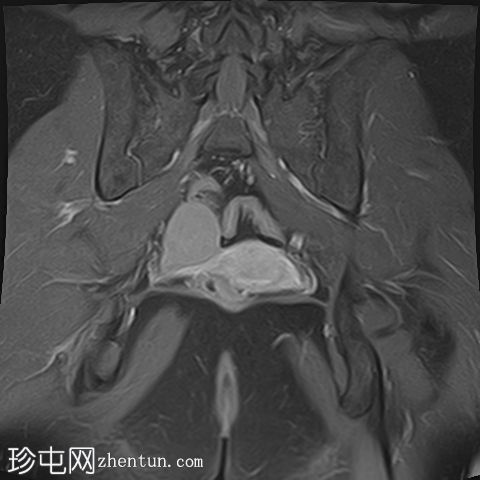

冠状位

T2

右侧卵巢出血性囊肿,T1成像呈中等信号,T2成像呈高信号,伴有薄内部分隔

左侧卵巢出血性囊肿,信号特征与右侧囊肿相似

左侧单纯性卵巢旁囊肿,T1成像呈低信号,T2成像呈高信号

此外,所有囊肿均未显示弥散受限或实性成分强化。

所有囊肿均仅显示薄层外周壁强化。

道格拉斯囊右侧可见轻度积液。

卵巢相关囊性病变边界相对清晰。信号特征可能因出血时间而异。

T1 加权成像:大多数病变呈低信号,也可能包含中至高信号成分。

T1 脂肪饱和度:通常显示中至高信号。

本例卵巢囊肿呈中等 T1 信号,类似于肌肉信号,T2 信号高,伴有薄内隔和外周壁强化。但无内部强化或弥散受限。STIR 序列显示与 T2 一致的信号,无任何脂肪成分。该表现提示卵巢出血性囊肿处于早期或消退期。

此外,左侧卵巢旁囊肿外观简单,T1 信号低,T2 信号高。

建议在下一个月经周期(通常在 6 至 8 周内)进行盆腔超声随访,以确保囊肿消退,因为大多数出血性囊肿往往会自行消退。如果病变持续存在或扩大,可能需要进一步评估。